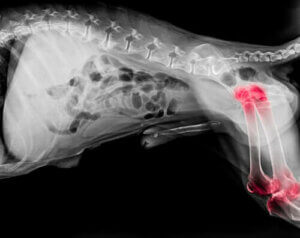

반려견의 관절염

전문가들은 반려견 5마리 중 1마리가 관절염으로 고통받는다고 추정한다. 관절 문제는 모든 나이대에서 나타나지만 노견의 발병률이 높은 편이다. 관절염은 팔꿈치와 어깨 관절 모두에 염증을 일으키는 퇴행성 질환이다.